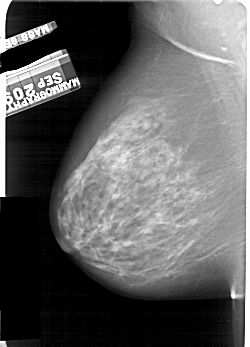

A_1859_1.LEFT_CC

LEFT_CC LINES 5461 PIXELS_PER_LINE 3586 BITS_PER_PIXEL 12 RESOLUTION 43.5 NON_OVERLAY